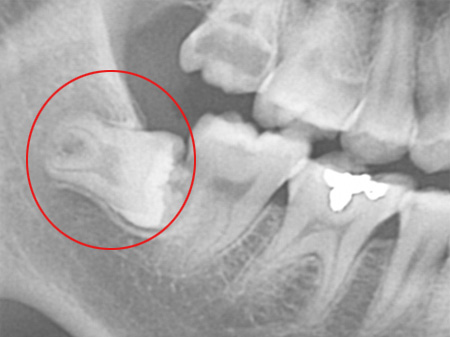

¸Åº¹ »ç¶û´Ï´Â ÅλÀ¿¡ °ø°£ÀÌ ÃæºÐÇÏÁö ¾Ê¾Æ »ç¶û´Ï°¡ ÀÕ¸öÀ» ¶Õ°í ¸ÍÃâµÇÁö ¸øÇϰí Ä¡Á¶°ñ ³»¿¡ ¸Åº¹µÈ °ÍÀ» ¸»ÇÕ´Ï´Ù. ÀÌ ¸Åº¹»ç¶û´Ï´Â Ä¡¾Æ°¡ ¿ÏÀüÈ÷ ¸ÍÃâµÇÁö ¾Ê¾Ò±â ¶§¹®¿¡ À½½Ä¹°ÀÌ »ç¶û´Ï ÀÕ¸ö ÇϹæÀ¸·Î °íÀÌ°Ô µÇ°í, Ä©¼ÖÁú·Îµµ Á¦´ë·Î Á¦°ÅµÇÁö ¾Ê¾Æ ÀÕ¸ö ¿°ÁõÀ» À¯¹ßÇÏ¿© »ç¶û´Ï´Â ¹°·Ð ÀÎÁ¢Ä¡¾Æ¿¡±îÁö ¼Õ»óÀ» ÀÔÈú ¼ö ÀÖ½À´Ï´Ù.

ÀÌ ¶§¹®¿¡ ¸Åº¹ »ç¶û´Ï´Â ¹ßÄ¡¸¦ ÇÏ´Â °ÍÀÌ °¡Àå ÁÁ½À´Ï´Ù. ´õÁÁÀº¼­¿ïÄ¡°ú¿¡¼­´Â ¿¢½º·¹ÀÌ Àåºñ, ÷´Ü CT µî´Â »ç¶û´Ï ¹ßÄ¡ Áø´Ü¿¡ ÇÊ¿äÇÑ Ã·´Ü Àåºñ¸¦ º¸À¯Çϰí ÀÖ¾î ¾ÈÀüÇÑ »ç¶û´Ï ¹ßÄ¡°¡ °¡´ÉÇÑ °ÍÀº ¹°·Ð ÀÓ»ó°æÇèÀÌ Ç³ºÎÇϱ⠶§¹®¿¡ ¾ÈÀüÇÏ°Ô »ç¶û´Ï ¹ßÄ¡¸¦ ¹ÞÀ¸½Ç ¼ö ÀÖ½À´Ï´Ù.